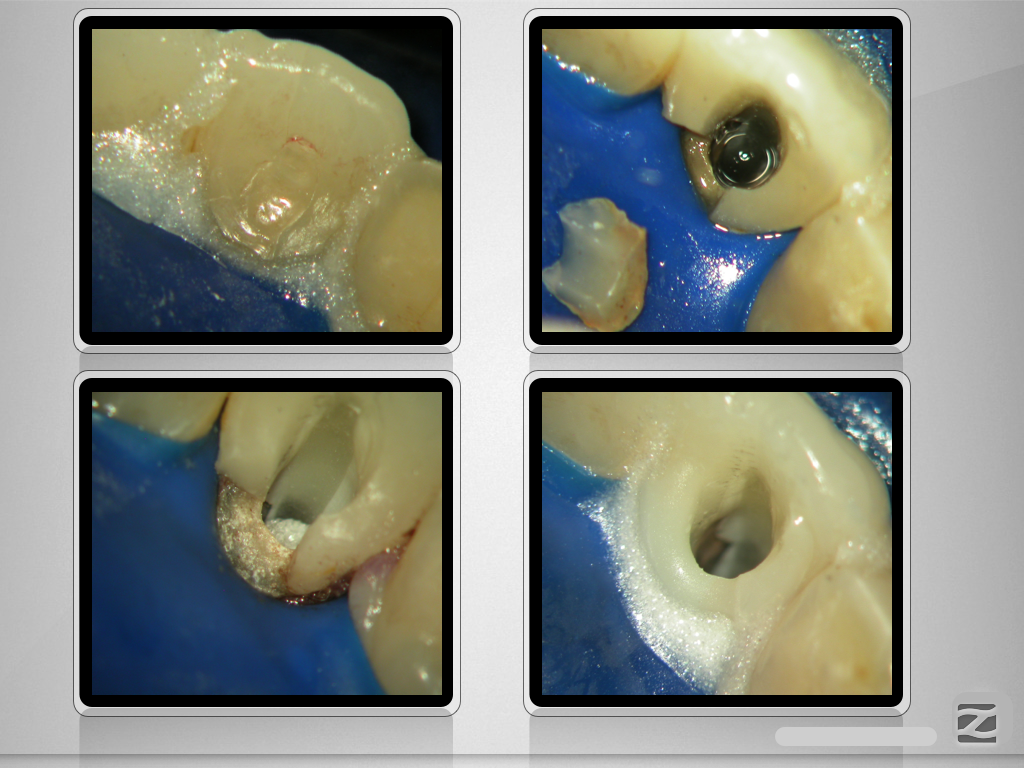

Der Schein trügt